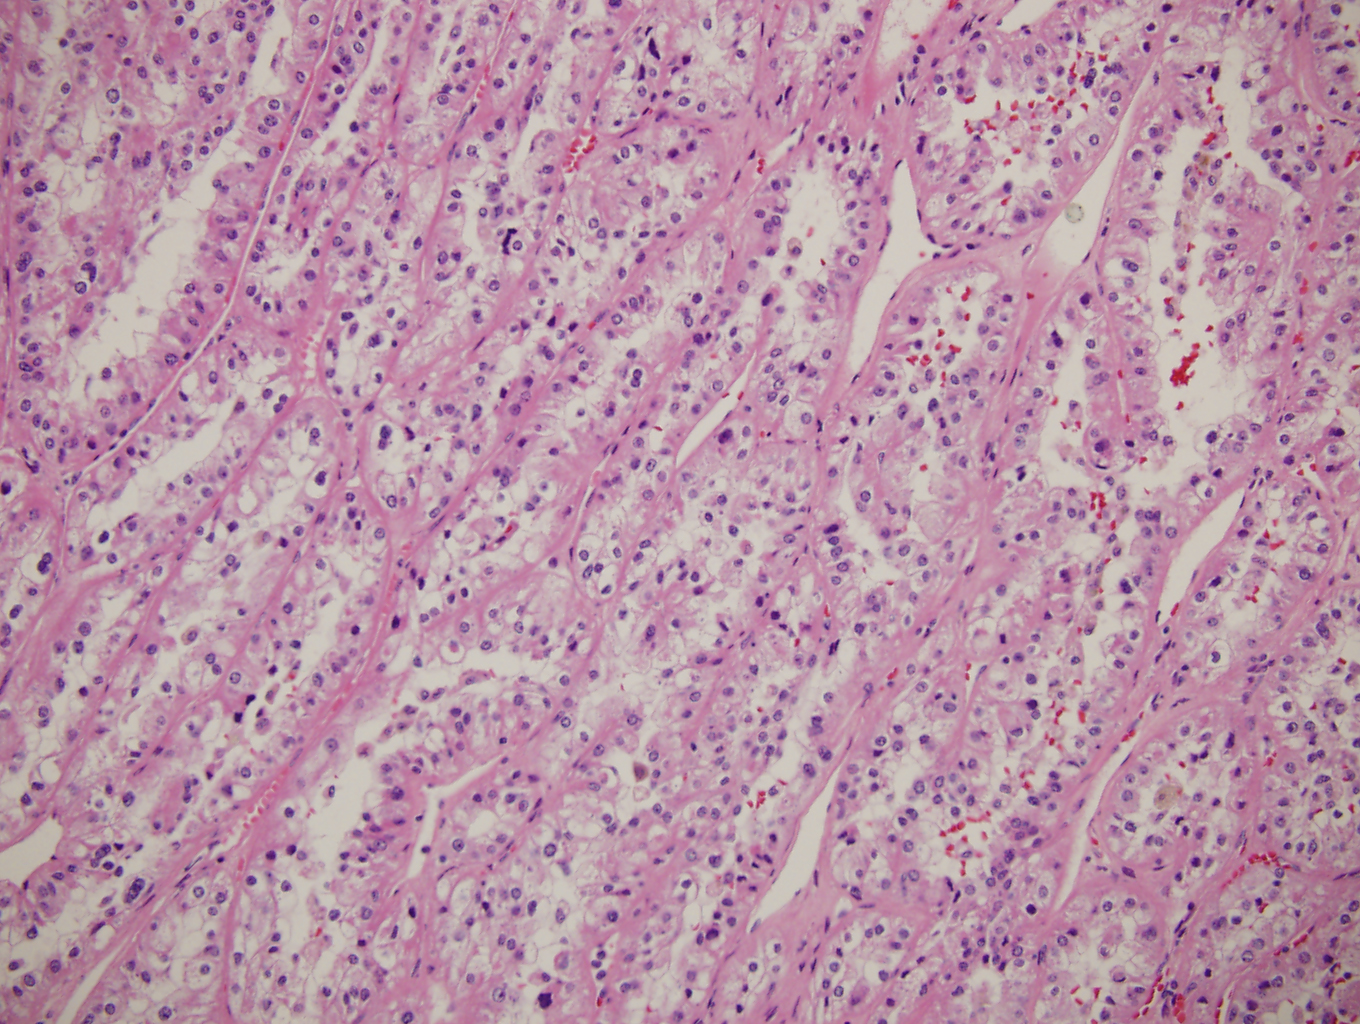

Case history

A pancreatic head mass was discovered in a 50-year-old man with chronic pancreatitis....